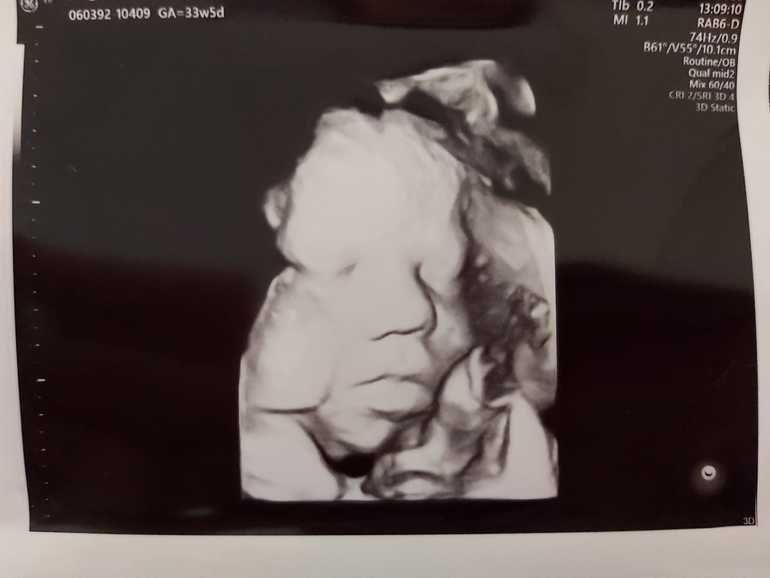

Вот наш сладкий малышик:

Малыш в 34 недели весит 2800 - крупный. Сказали к родам будет под 4 кг. Ух.....😳

И по замерам малыш все так же опережает а 1-2 недели.

Первый раз поставили многоводие, но пока тоже не критично, чуть расширены петли кишечника, контрольное УЗИ через 2 недели. 😬

Плацента 2 степени зрелости, доплер в норме.